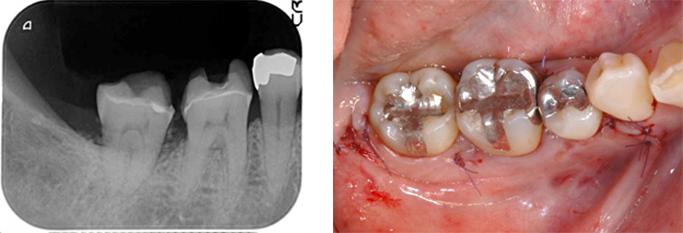

大臼歯に狭く深い骨欠損が見られる48歳女性

BEFORE(初診時)

右下奥歯が腫れると来院。最奥歯の周囲の骨が狭くやや深くなくなっています。

術前のレントゲンでも歯の周囲の骨が不整であることが理解できます。

カラー写真だと一見したところ異常が無い様に思えますが、、、

※血が苦手な方に配慮して画像の色味を修正しています。

歯肉を切開し骨をあらわにしたところ、最奥歯の骨の欠損が確認できます。

AFTER ( 術中・術後 )

欠損部にエムドゲイン、周囲から採取した骨を填塞し、その上に膜(バリアメンブレン)を設置しています。

この方の場合は手前の歯のすり減り等を考慮すると歯ぎしりなどの噛む力のコントロールがなされていない、または噛み合わせが悪く現状に至ったと推察しました。

基本治療から3ヵ月しても改善が見られなかったため再生療法を施術し現在も加療中です。